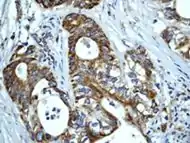

As well as influencing apoptosis, HSP60 changes in expression level have been shown to be “useful new biomarkers for diagnostic and prognostic purposes.” [23] According to Lebret et al., a loss of HSP60 expression “indicates a poor prognosis and the risk of developing tumor infiltration” specifically with bladder carcinomas, but that does not necessarily hold true for other types of cancers.[25] For example, ovarian tumors research has shown that over expression is correlated with a better prognosis while a decreased expression is correlated with an aggressive tumor.[25] All this research indicates that it may be possible for HSP60 expression to be used in predicting survival for certain types of cancer and therefore may be able to identify patients who could benefit from certain treatments.[24]